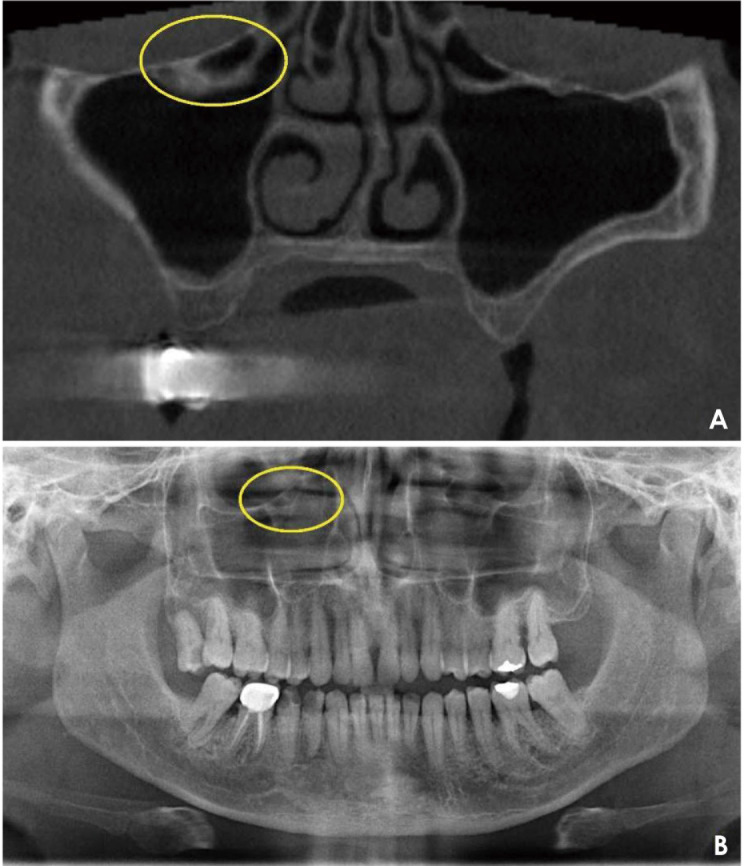

Purpose: Haller cells (HCs) represent an anatomical variation in the maxillofacial region, frequently linked to sino-nasal pathologies. Numerous regional studies have reported the prevalence of HCs using various imaging modalities. This systematic review aims to evaluate the prevalence of HCs as reported in the existing literature.

Results: After data extraction, 9 studies qualified for critical analysis. The highest reported prevalence of HCs was 66.84%, whereas the lowest was 16%. Across these 9 studies, the average prevalence was 32.40%. Unilateral HCs predominated in most reported studies. Four studies provided details regarding the shapes of HCs, while size information was available in three studies. Eight of the 9 included studies demonstrated strong evidence quality according to the CASP checklist.

Conclusion: Approximately one-third of radiographic scans analyzed in published studies revealed the presence of HCs. Unilateral HCs were found to be more common than bilateral HCs. The most frequently reported shapes were round, ovoid, and teardrop, with the majority measuring between 2 and 4 mm.